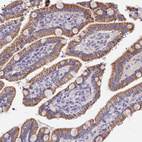

Immunohistochemical staining of human fallopian tube shows moderate cytoplasmic positivity in glandular cells.